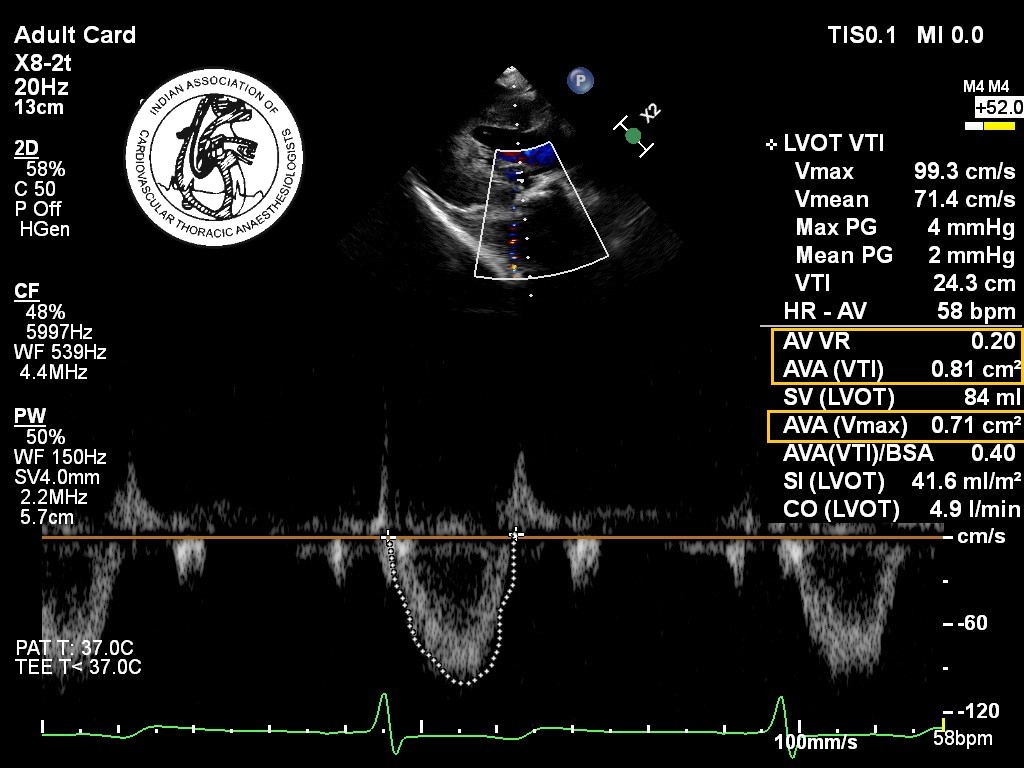

A 60-years-old asymptomatic patient (body surface area 1.5 m2) is diagnosed with severe aortic stenosis. During intraoperative transesophageal echocardiographic examination, the following data are obtained: LVOT peak velocity = 0.6m/s; LVOT velocity time integral (VTI) = 14 cm; LVOT diameter = 1.9 cm; peak velocity across aortic valve = 3m /s; aortic valve VTI = 74 cm, LV ejection fraction of 45%. The patient has a heart rate of 55/min during the study. All of the following statements are correct except:

3.Aortic valve area (Continuity equation)

Aortic valve area= LVOT cross sectional area x LVOT VTI / aortic valve VTI

= 2.84 X 14 / 74

=0.54 cm2

4.Final summary:   Mean gradient = 23 mmHg

Stroke volume index = 26.7 ml/m2

Cardiac output = 2.2 L/ min

Aortic valve area= 0.54 cm2

It is consistent with Low-flow, low-gradient severe aortic stenosis,  as the ejection fraction is 45%.

Correct Answer: d)It is a classic example of moderate aortic stenosis.